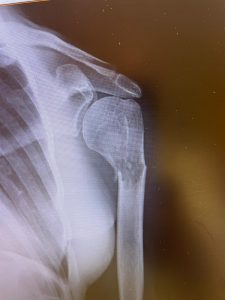

- Diagnóstico por imagen: Radiografías, resonancias magnéticas (RM), tomografías computarizadas (TC) y gammagrafías óseas ayudan a localizar y evaluar la extensión de las metástasis.